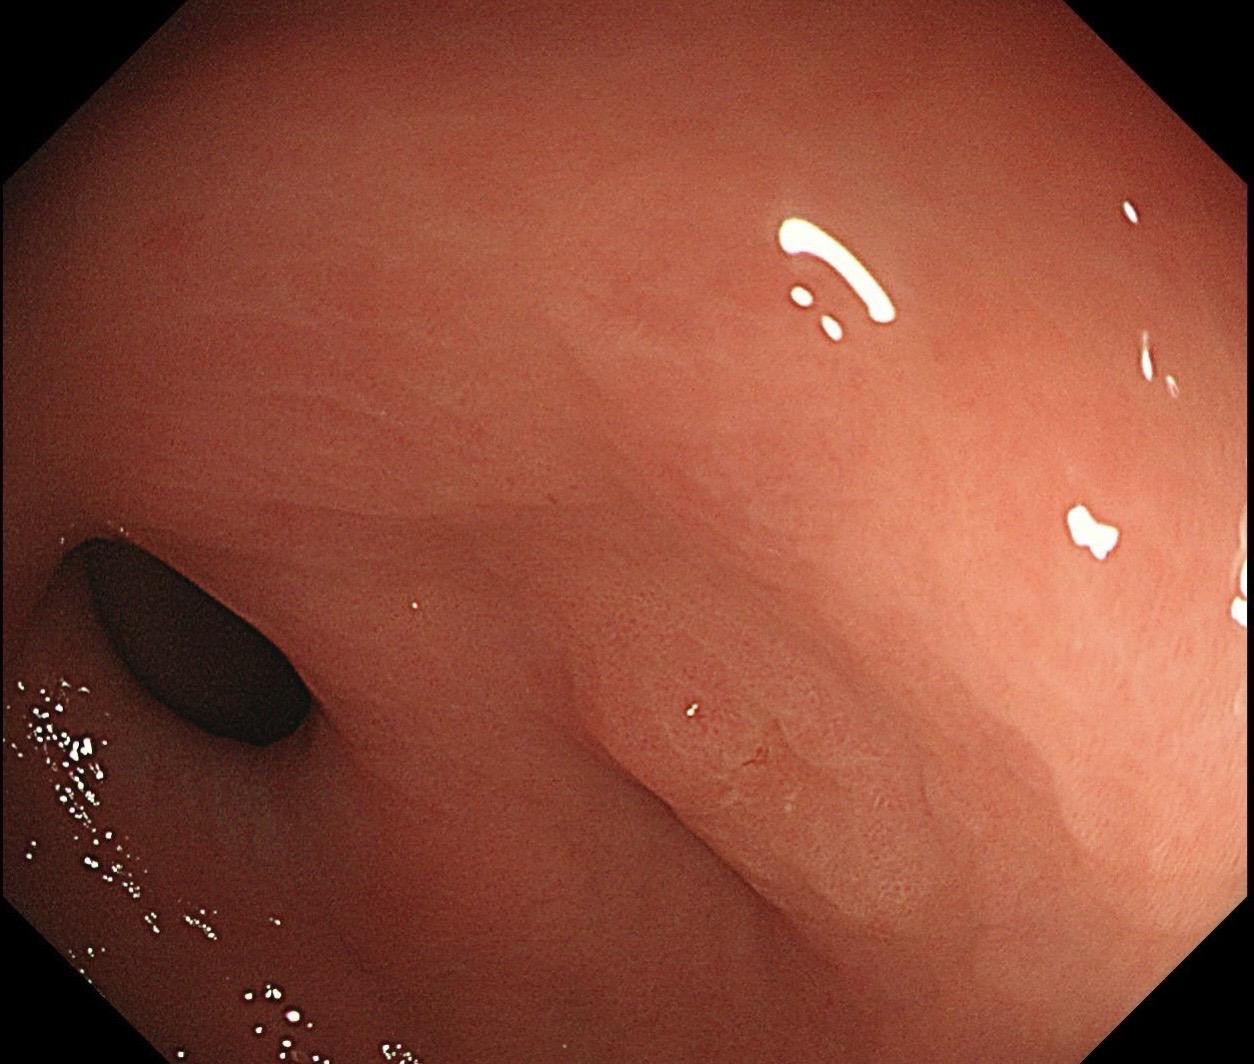

萎缩背景,注意那些微小的发黄色调。